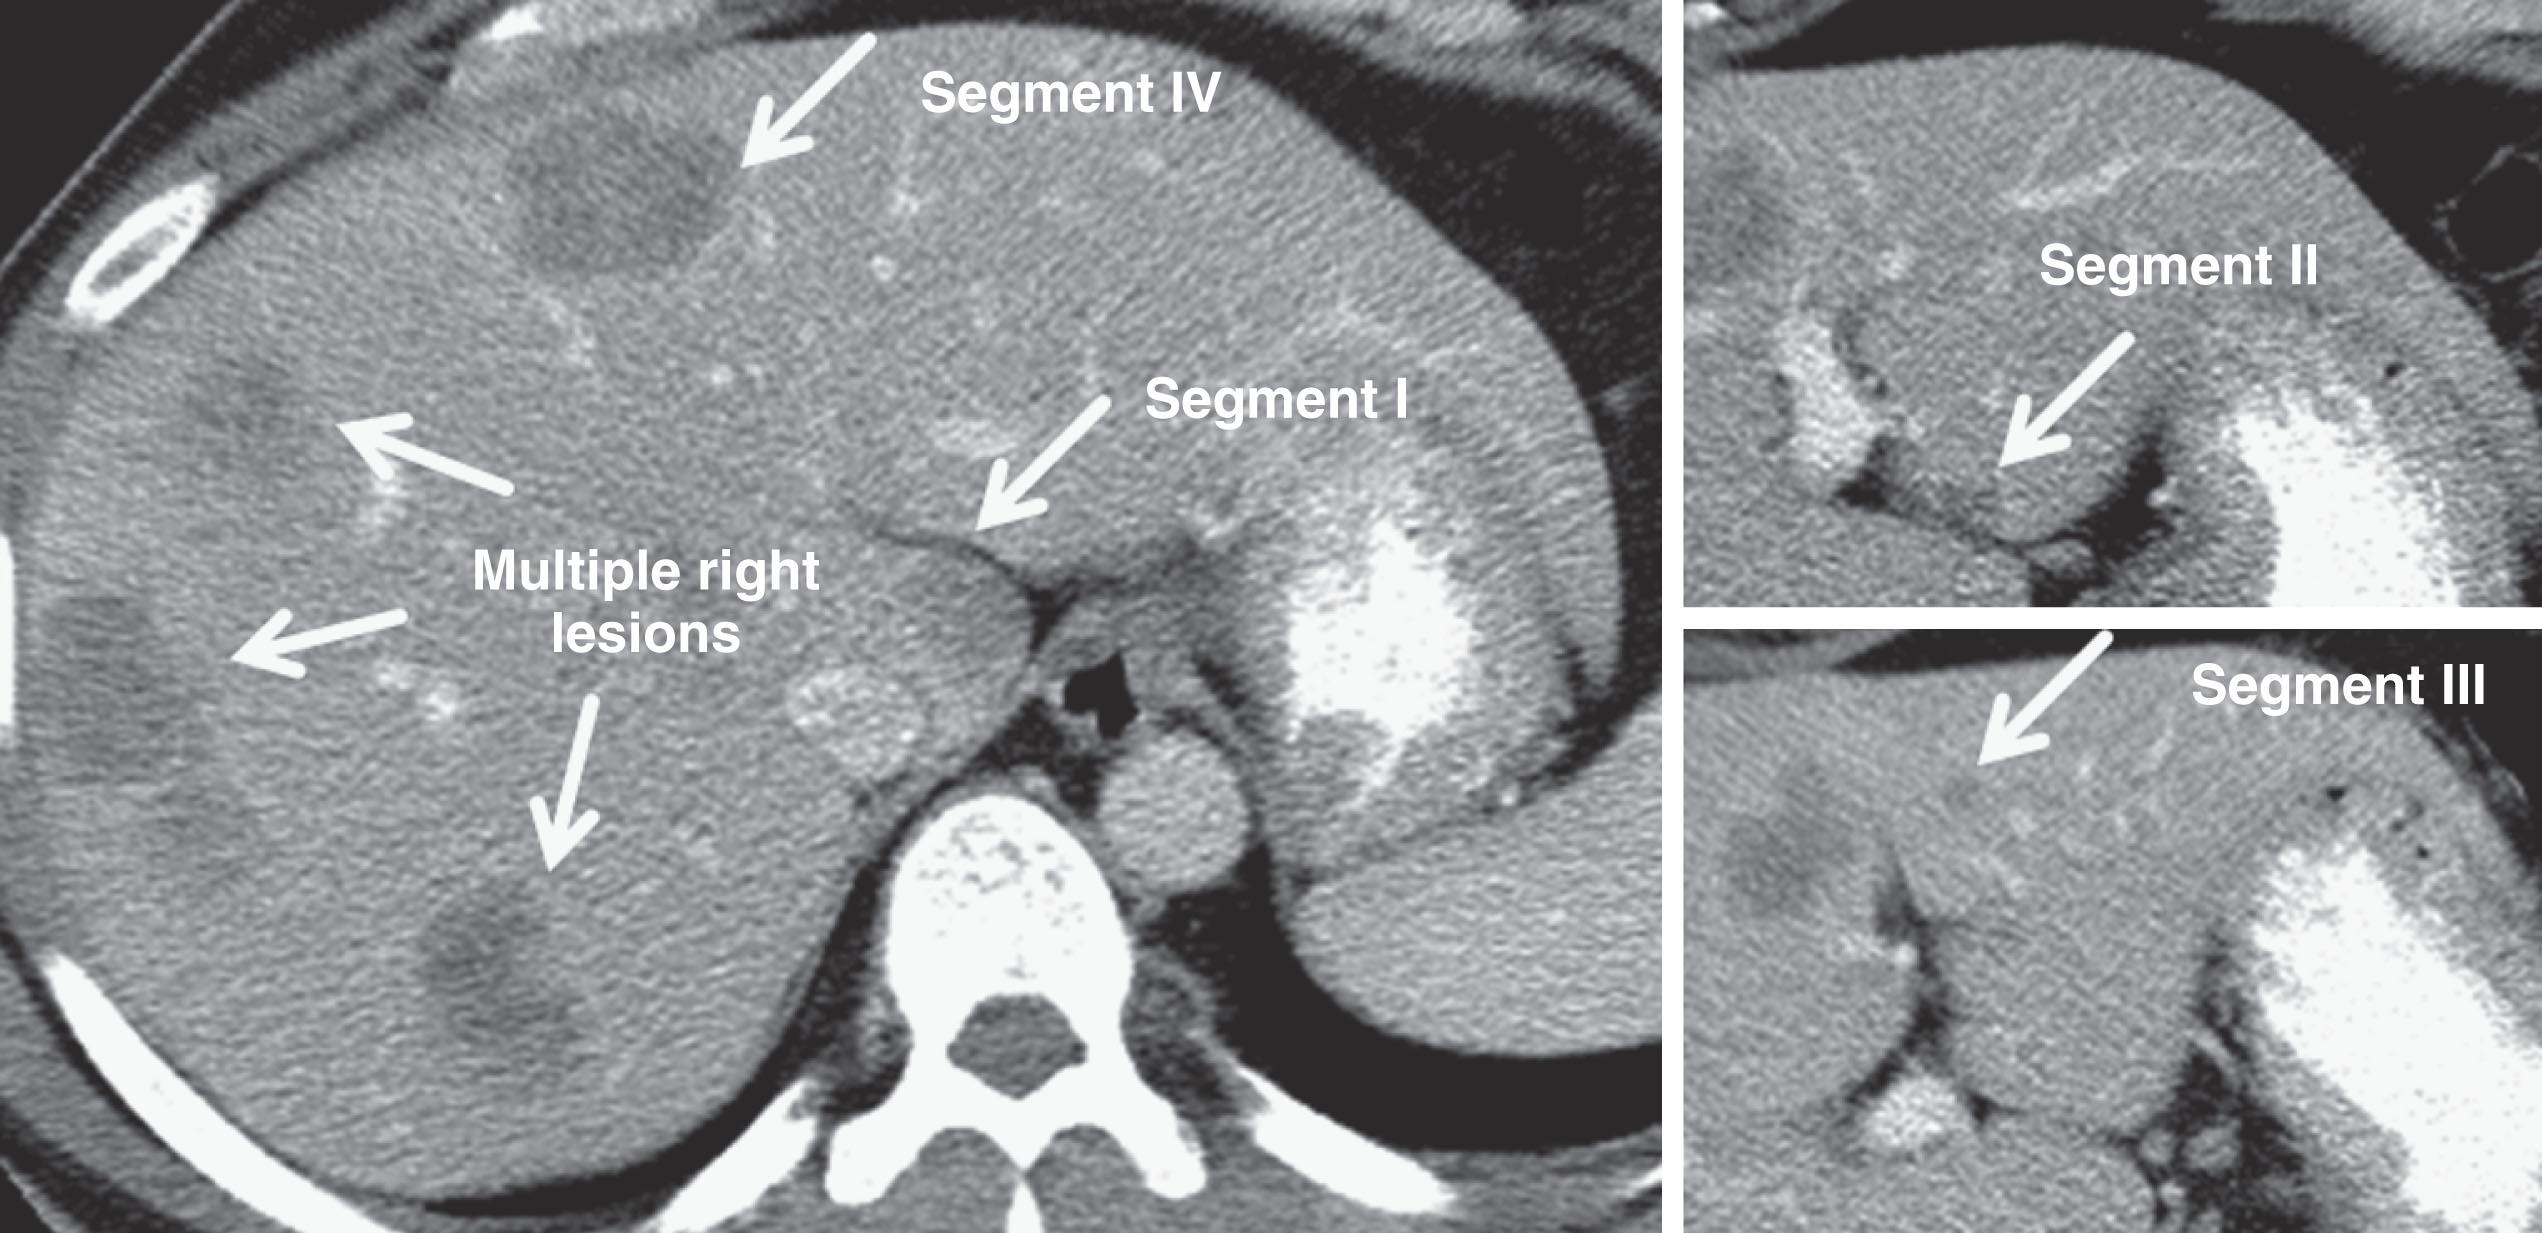

Thus surgeons and radiologists must understand the anatomy of the liver (the hepatic veins, portal veins, and hepatic arteries) and must remark variations including replaced or accessory hepatic arteries (present in up to 55% of patients) or even the existence of important venous variants (e.g. inferior hepatic veins). Segmental liver volume is highly variable, which impacts surgical planning ; and tumor involvement of intrahepatic vessels or portal structures, as well as therapy changes, can alter volume distribution among hepatic segments. Systematic liver volumetry based on cross-sectional imaging and/or functional imaging is a critical tool to surgical planning for major liver resection, reiterating the intersection of radiologists and surgeons in surgical planning, although liver volumetry is typically requested by the surgeon to facilitate surgical planning that leaves specific adjacent anatomical liver segments intact. Radiologists and surgeons who work together are aware of the importance of anatomic variations and tumor–vessel relationships, and that these factors can lead to different radiological reports that guide patients and clinicians with the help of high-quality imaging and interpretation. An example synthesizing these issues in a patient with multiple bilateral colorectal liver metastases is illustrated in Fig. 2.1 .

Figure 2.1, This patient with a synchronous presentation of obstructing colon cancer and multiple bilateral colorectal liver metastases presented with a total of 16 tumors involving every anatomic segment of the liver, including the caudate (segment I). Resection was possible because the lateral liver was relatively spared; after chemotherapy with response, he underwent first-stage wedge resections of the segment II and III lesions, followed by right portal vein embolization extended to segment IV, followed by second-stage extended right hepatectomy with caudate lobectomy. He never experienced recurrence in the liver.